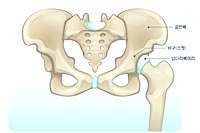

고관절은 골반을 지탱하는 중요한 관절로, 근육과 힘줄로 구성되어 있습니다. 학계에서는 이를 엉덩이 관절이라고 부르며, 신체의 하중을 지탱하는 중요한 역할을 합니다. 고관절은 우리가 정상적으로 서고 움직일 수 있도록 도와주며, 달리기, 점프, 무거운 물건을 들 때 최대 체중의 2~10배에 달하는 압력을 견딥니다. 따라서 적절한 관리가 필요합니다. 오늘은 고관절에서 나타날 수 있는 고관절 통증 증상 10가지에 대해 알아보겠습니다.

고관절 통증의 주요 원인은 퇴행성 질환으로, 나이가 들면서 관절 손상이 발생하는 것입니다. 고관절 자체의 구조적 문제, 주변 근육과 인대의 문제, 척추와 골반 문제 등 다양한 원인이 있습니다. 퇴행성 고관절염, 대퇴골두 무혈성 괴사, 대퇴골 경부 골절, 퇴행성 관절염, 급성 활액막염 등이 주요 원인입니다. 이러한 질환들은 심각한 합병증을 유발할 수 있어 빠른 치료가 필요합니다.